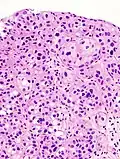

Immunohistochemistry for p53 can help distinguish a PUNLMP from a low grade urothelial carcinoma. Overexpression is seen in 75% of low-grade urothelial carcinomas and only 10% of PUNLMP.[12][13]

12. ^ Image is taken from following source, with some modification by Mikael Häggström, MD:

- Schallenberg S, Plage H, Hofbauer S, Furlano K, Weinberger S, Bruch PG; et al. (2023). "Altered p53/p16 expression is linked to urothelial carcinoma progression but largely unrelated to prognosis in muscle-invasive tumors". Acta Oncol. 62 (12): 1–10. doi:10.1080/0284186X.2023.2277344. PMID 37938166.{{cite journal}}: CS1 maint: multiple names: authors list (link)

13. ^ Source for role in distinguishing PUNLMP from low-grade carcinoma:

- Kalantari MR, Ahmadnia H (2007). "P53 overexpression in bladder urothelial neoplasms: new aspect of World Health Organization/International Society of Urological Pathology classification". Urol J. 4 (4): 230–3. PMID 18270948.